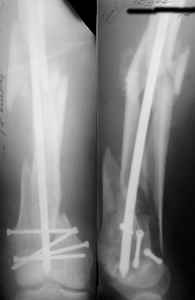

1. Percutaneous nailing is truly minimally invasive technique, but, unfortunately, nails are not reliable in many hands.

Attached are few examples from our Hospital:

A. Difficult reductions, even in retrograde nailing (my preference, easier control of "small" distal fragment) and it is much, much harder to do it anterograde (Alex, do you have one good case in your collection of anterograde nailing in very distal fractures - as you have suggested that I

should have done it in my previously posted case?

Malpositioning is much too common (recurvatum, varus - valgus).

B. Fixation loosening: distal cutting of the nail, non-unions do happen (cases attached).

Locking Plating has more distal screws than any nail, fixed angles and provides much better fixation, especially in osteoporotic bone.